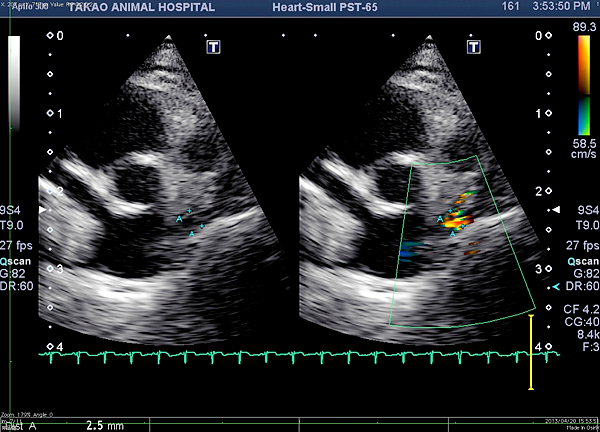

下記は当院での実際の症例です。 この症例は猫ですが、肥大型心筋症も合併していたため左心房圧の上昇によりエコー検査において心房中隔欠損が診断できた症例です。

• 図1 心房中隔から左心房から右心房内に短絡血流が認められます。